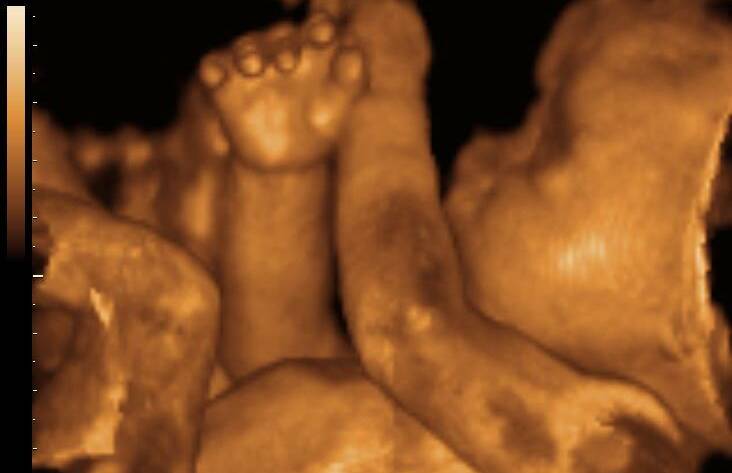

4 boyutlu ultrason nedir ve diğerlerinden farkı nedir?

4 boyutlu ultrason, bebeğin anne karnındaki hareketli görüntüsünü gerçek zamanlı olarak sunan ileri düzey bir görüntüleme teknolojisidir.

“Dördüncü boyut” burada zamanı ifade eder; yani bebeğin 3 boyutlu görüntüsüne ek olarak hareketlerini de canlı olarak izleyebilirsiniz.

Standart 2 boyutlu ultrasonlarda siyah-beyaz kesit görüntü alınırken, 4 boyutlu ultrason sayesinde bebeğin mimikleri,…